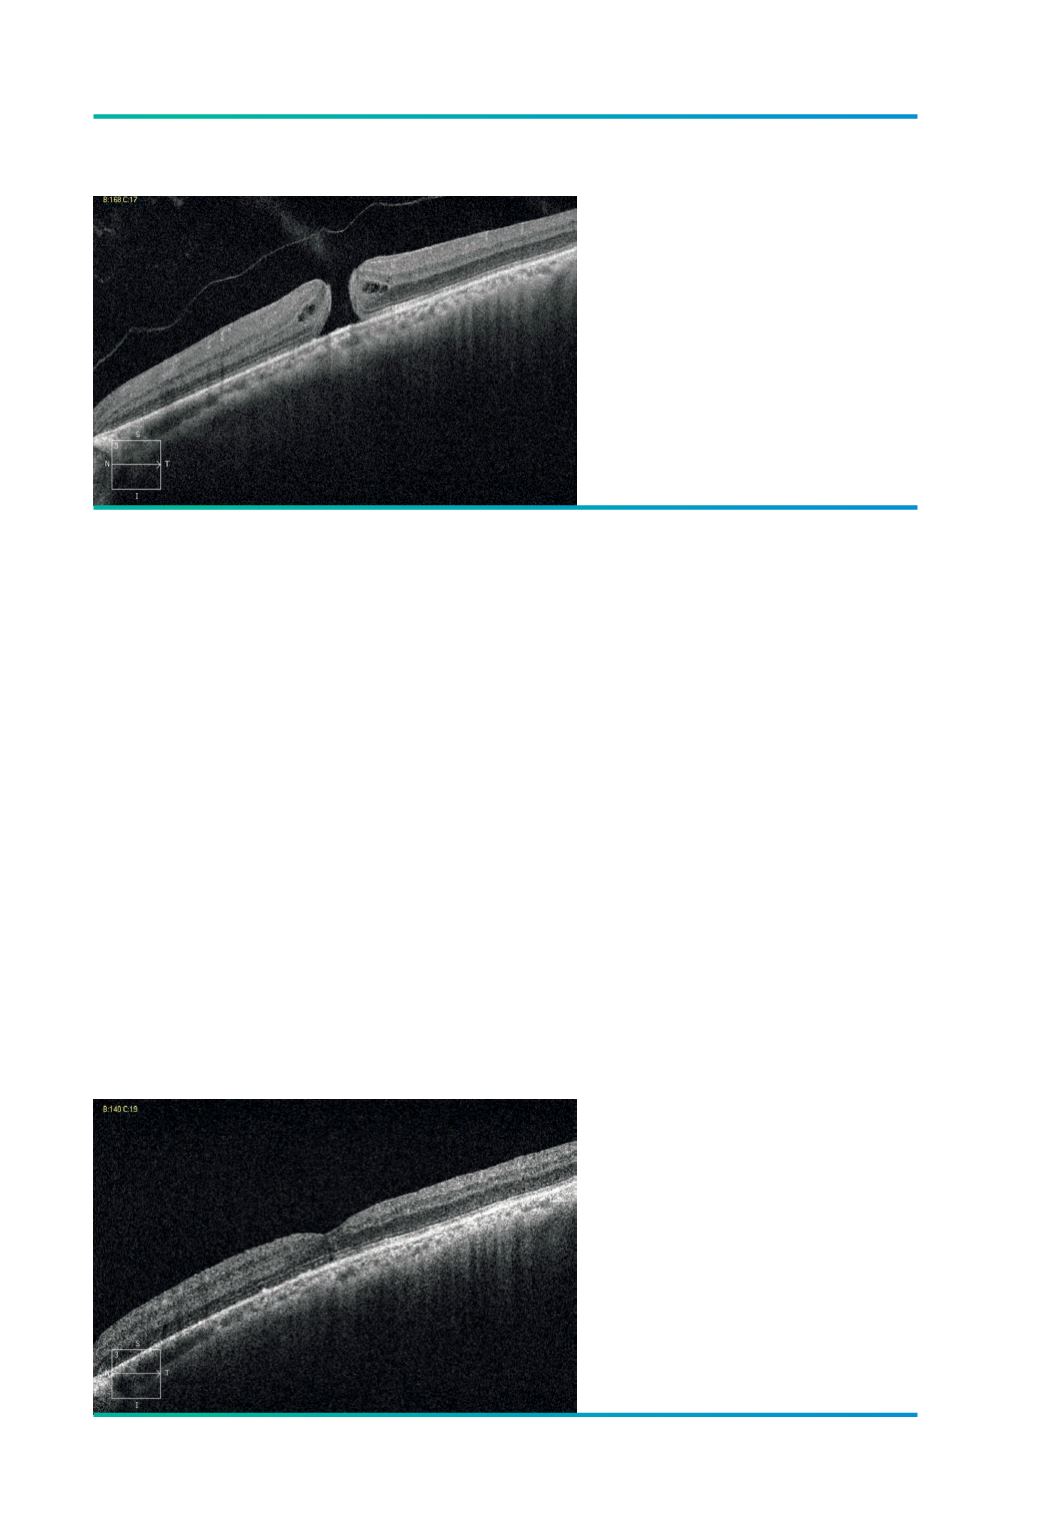

O BMM com um aspecto no OCT se-

melhante ao buraco macular idiopático

,

não associado a retinosquisis, apenas com

os bordos espessados e com alguns cistos

retinianos (Figuras 5 e 6), geralmente aparece

Figura 5.

Buraco Macular Miópico Miopia - 7.50 D

C.Ax- 28,6 mm.

Figura 6.

Um ano após vitrectomia, pelagem da

MLI, tamponamento com gás.